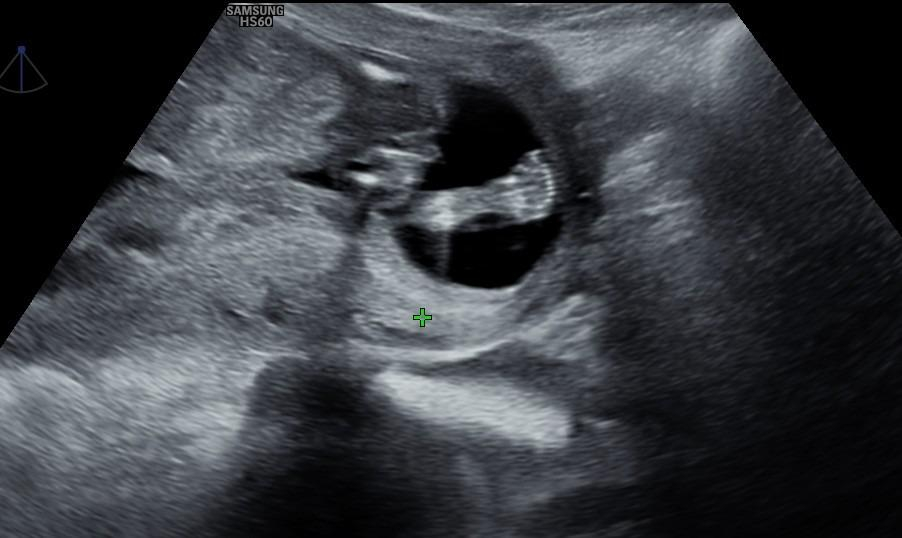

ich hatte mein Ersttrimesterscreening (Ssw 12+3) kann man hier den Nub erkennen und dann vielleicht auch das Geschlecht?

Würde mich so über eine Antwort freuen.

Vielen lieben Dank

Ich würde Mädchen raten.

Siehst du wirklich eher ein Mädchen? Darf ich vielleicht fragen, warum du dazu tendierst? Entschuldigung aber ich bin ganz aufgeregt 🥰

Ich hab auch gedacht ich sehe einen Nub aber eher einen Jungen, weil er so gestapelt aussieht?

Ich freue mich so sehr über beides, aber ein Mädchen wäre einfach noch ein Traum nach meinen Goldjungs 🥰.